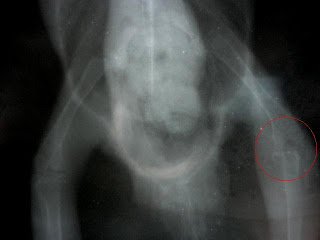

OSTECTOMÌA CABEZA FÈMUR (LUJACIÒN CRÓNICA DE CADERA)

PACIENTE REMITIDO A NUESTRA CLÍNICA DEBIDO A CLAUDICACIÓN CRÓNICA DE MPD; HACE DOS SEMANAS FUE ENCONTRADO POR SUS DUEÑOS, NO APOYA MPD, FUE ATENDIDO Y RECIBIÓ UN TRATAMIENTO INICIAL CON ANALGÉSICOS Y ANTIINFLAMATORIOS SIN RESULTADO POR LO CUAL FUE REMITIDO A ESTUDIO RADIOLÒGICO ENCONTRÁNDOSE LUJACIÓN CRANEODORSAL DE MPD. DEBIDO A LA CRONICIDAD , TAMAÑO Y PESO DEL PACIENTE SE PROCEDIÓ A UNA OSTECTOMÌA CORRECTIVA.